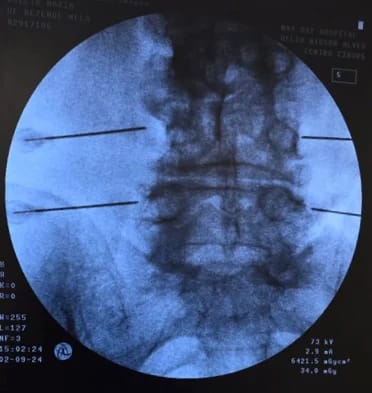

Bloqueio ou Infiltração Guiada por Imagem

Procedimento de alta precisão para alívio da dor, que consiste na injeção de medicamentos (anestésicos e/ou anti-inflamatórios) diretamente na fonte do problema, como um nervo, uma articulação ou tendão. O uso de ultrassom ou raio-x em tempo real para guiar a agulha garante que a medicação seja entregue no local exato, maximizando a eficácia, a segurança e podendo também auxiliar no diagnóstico preciso da causa da dor.

Benefícios:

- Máxima Precisão do Alvo

- Alívio Rápido e Eficaz

- Auxilia no Diagnóstico

- Procedimento Minimamente Invasivo